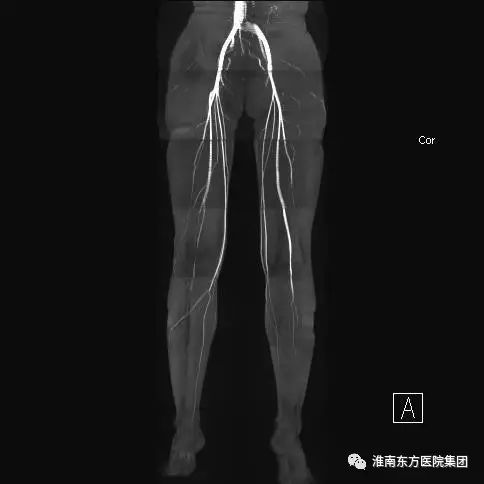

下肢静脉

三、36通道的下肢血管线圈使大范围的下肢动静脉血管不用打药、一次性成像成为现实。